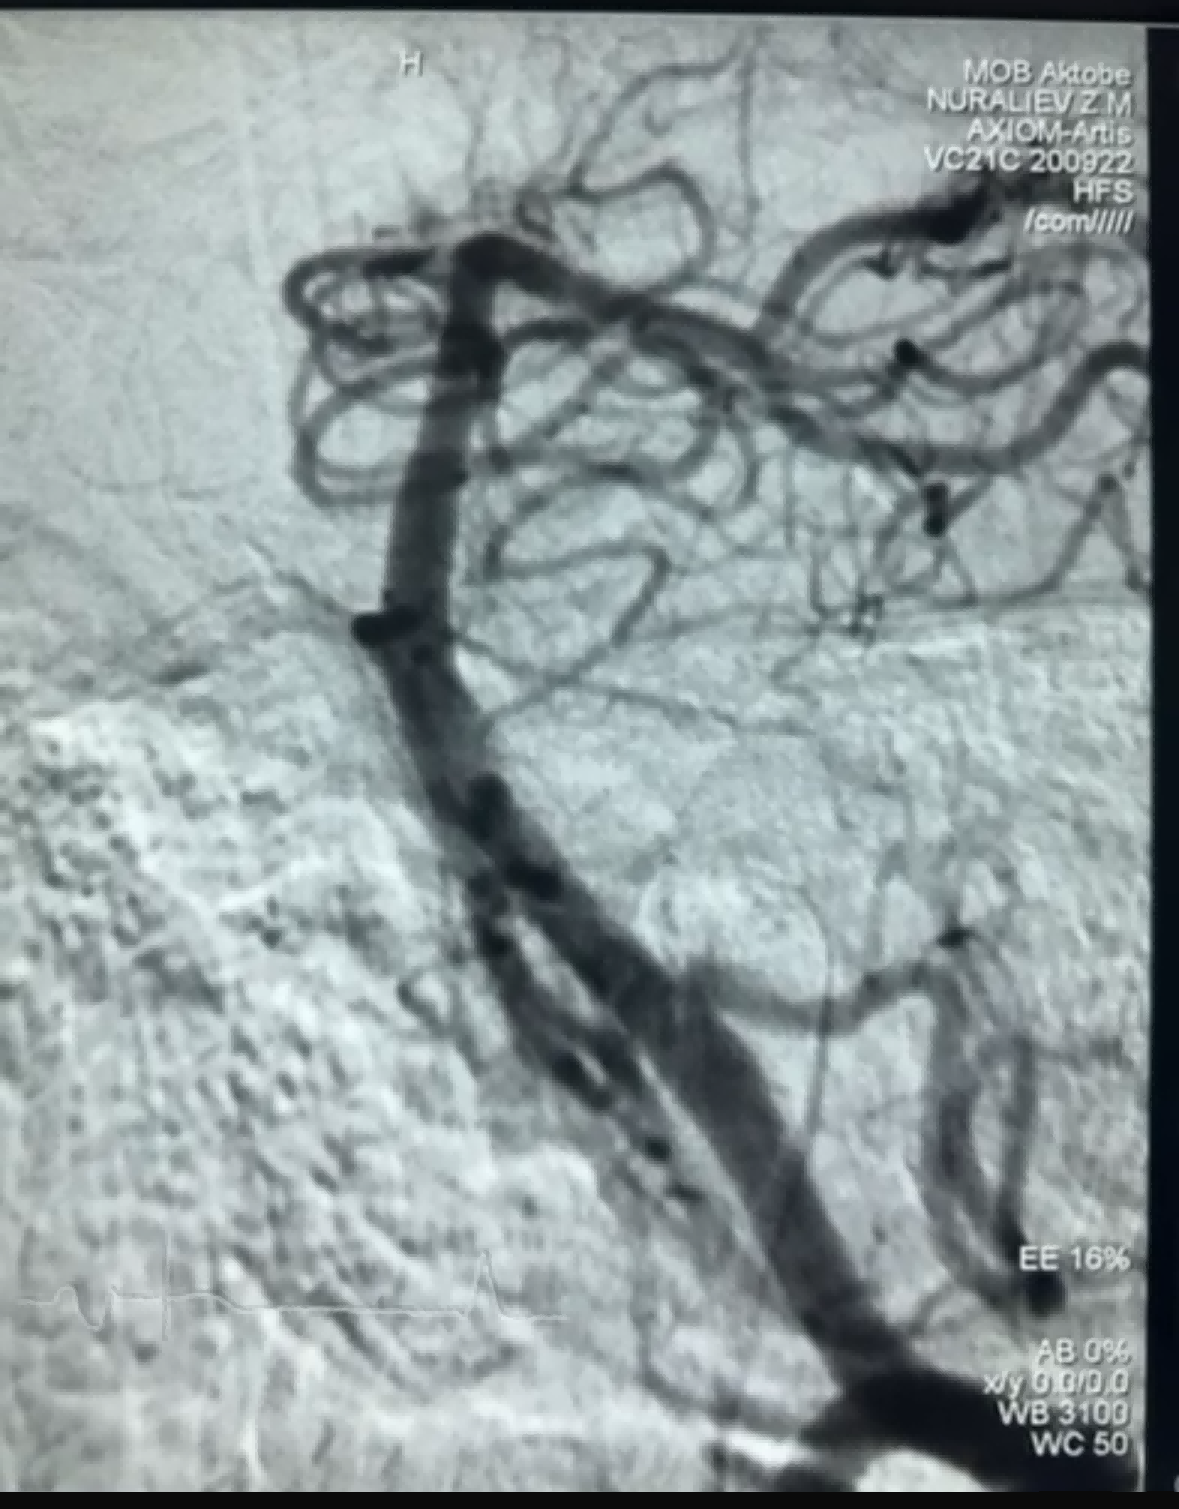

Hiljuti oli edukas trombektoomia juhtum, kus kasutati NeuroSafe Medical Co., Ltd. firma Dredger Stent Retriever. Dredger Stent Retrieveril on mitteinvasiivne pehme ots, mis vähendab oluliselt intimakahjustuse ohtu, ja sellel on ainulaadne erikujuline auk. disain, mis lööb verehüübed peamiselt kinni vahemuutused.